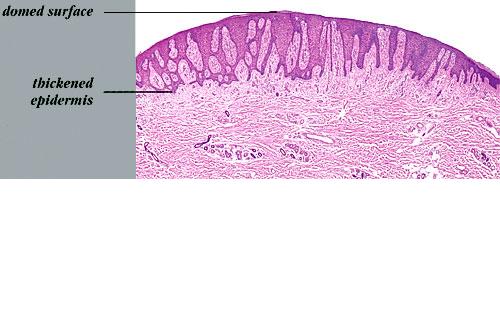

Pale cell acanthoma = شوكوم الخلايا الشاحبة